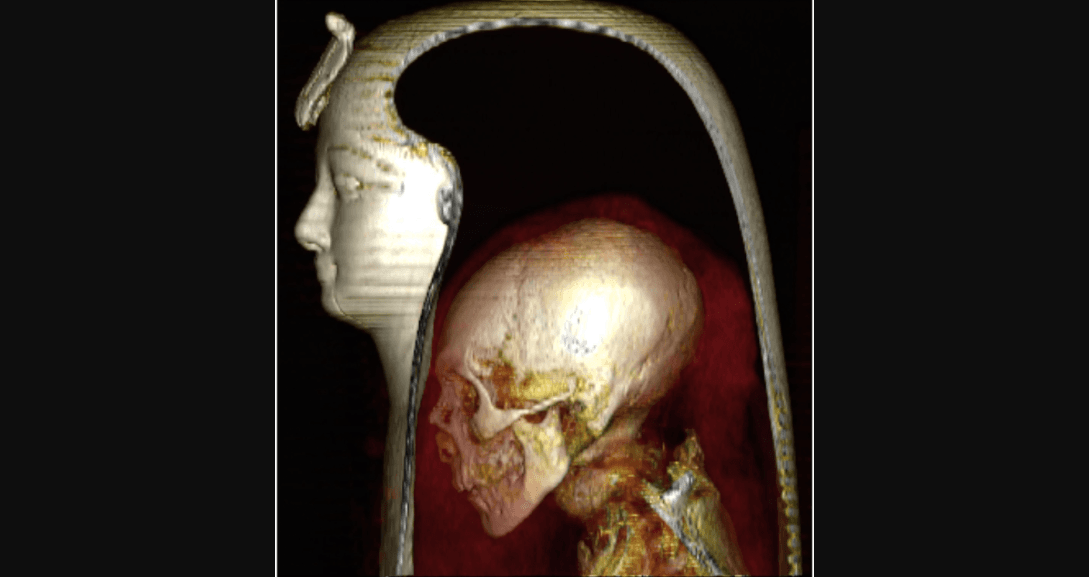

El misterio en torno a la apariencia del faraón egipcio Amenhotep I ha sido develado gracias a la tecnología de una tomografía computarizada en 3D realizada por un grupo de expertos de la Universidad de El Cairo.

Investigadores egipcios han desenvuelto gracias a la tecnología digital los restos momificados del faraón Amenhotep I, revelando detalles valiosos sobre su vida y muerte por primera vez desde que se descubrió la momia en 1881.

En un estudio publicado este martes en la revista científica Frontiers in Medicine, se develan los detalles encontrados tras el escaneo al cuerpo momificado de este rey desubierto en 1881 y uno de los pocos que aún no había sido desenvuelto en la modernidad.

Su hogar actual es el Museo Egipcio de El Cairo y no ha sido desenvuelto físicamente debido a los envoltorios de lino "perfectos" cubiertos por guirnaldas de delfinios, cáñamo egipcio y cártamo, además de la belleza de su máscara funeraria pintada.